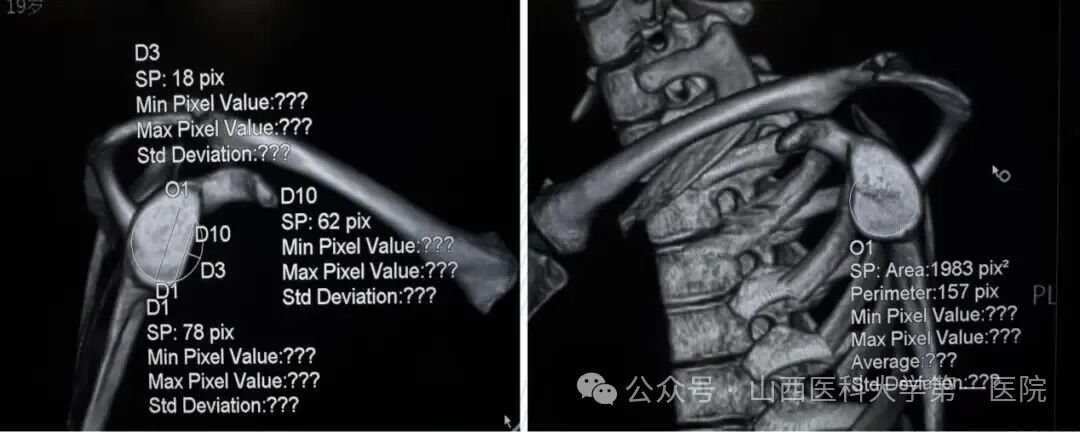

术前,患侧肩关节盂与健侧相比,缺损约25%